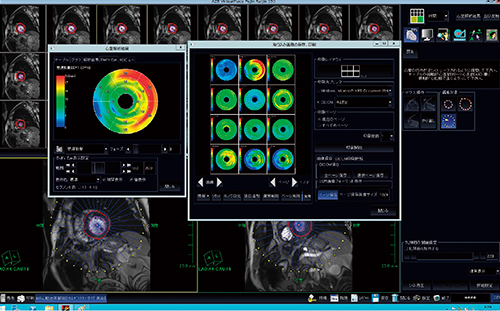

5.Cardiac MR

当院における心臓撮像は月間10例ほどであるが,その8割はATP負荷を含めたone stop shopである。解析は,VirtualPlaceを用いてBull's eyeの心機能解析や冠動脈解析,フロー解析などを行っている。画像はすべてMRI担当技師が作成しており,時に描出能に関して他社製WSとの比較も行っている(図5)。

図5 Bull's eyeなどによる心機能解析